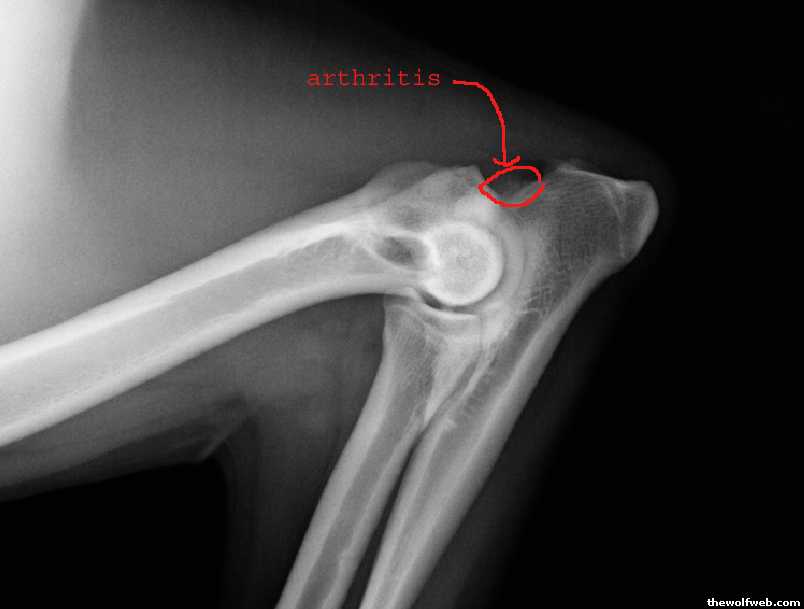

here are her xrays...

the fragmented piece, circled.

the typical arthritis caused by this broken piece